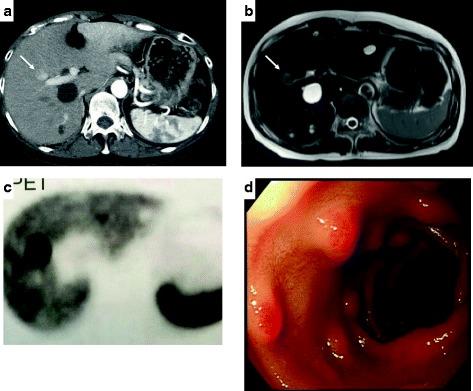

A 57-year-old woman consulted a clinic complaining of melena, intermittent abdominal pain, diarrhea, and vomiting which had persisted for about 3 years. Six months before her presentation, she underwent segmental resection of the jejunum for acute peritonitis due to the spontaneous jejunal perforation. A blood test revealed that her serum immunoreactive gastrin (IRG) level was 12,037 pg/mL. Subsequently, she was transferred to our hospital. On computed tomography (CT), a hypervascular tumor of 23 mm in the segment 5 (S5) region of the liver was visualized. A selective arterial secretagogue injection test (SASI test) was performed twice. The first SASI test revealed that the hepatic tumor was a gastrinoma, and there was no gastrinoma in the duodeno-pancreatic region. Additionally, somatostatin receptor scintigraphy only visualized the tumor in the liver. However, the second SASI test, which was performed during the administration of a proton pump inhibitor and a somatostatin analog (octreotide acetate), revealed that there may have been gastrinomas existing not only in the liver but also in the upper part of the duodenum or the head of the pancreas. Duodenal endoscopy revealed multiple submucosal tumors in the first and the second portion of the duodenum, although a pathological examination of biopsied specimens obtained from the duodenal lesions was negative for malignant cells. Multiple endocrine neoplasia type 1 (MEN1) was excluded from her family history, and serum levels of both intact parathyroid hormone (iPTH) and calcium were within normal ranges. An anterior segmentectomy of the liver and pancreas-preserving total duodenectomy were performed on September 9, 2013. Postoperatively, her serum immunoreactive gastrin level decreased to less than 50 pg/mL. Pathological study of the resected specimens revealed a gastrinoma in the liver, but no gastrinoma in the duodenum. Interestingly, the duodenal submucosal tumor-like lesions were hyperplastic Brunner's glands. Postoperatively, she has been well without recurrence of hypergastrinemia for 4 years.

一名57岁女性因黑便、间歇性腹痛、腹泻和呕吐持续约3年就诊于诊所。就诊前6个月,她因自发性空肠穿孔导致急性腹膜炎接受了空肠节段切除术。血液检查显示其血清免疫反应性胃泌素(IRG)水平为12,037 pg/mL。随后,她被转至我院。在计算机断层扫描(CT)检查中,肝脏第5段(S5)区域可见一个23 mm的富血管肿瘤。进行了两次选择性动脉促分泌素注射试验(SASI试验)。第一次SASI试验显示肝脏肿瘤为胃泌素瘤,十二指肠 - 胰腺区域无胃泌素瘤。此外,生长抑素受体闪烁显像仅显示肝脏中的肿瘤。然而,在给予质子泵抑制剂和生长抑素类似物(醋酸奥曲肽)期间进行的第二次SASI试验显示,不仅肝脏中可能存在胃泌素瘤,十二指肠上部或胰头也可能存在胃泌素瘤。十二指肠内镜检查发现十二指肠第一和第二部分有多个黏膜下肿瘤,尽管从十二指肠病变获取的活检标本病理检查未发现恶性细胞。其家族史排除了1型多发性内分泌腺瘤病(MEN1),血清完整甲状旁腺激素(iPTH)和钙水平均在正常范围内。2013年9月9日进行了肝脏前段切除术和保留胰腺的全十二指肠切除术。术后,她的血清免疫反应性胃泌素水平降至低于50 pg/mL。切除标本的病理研究显示肝脏中有胃泌素瘤,但十二指肠中无胃泌素瘤。有趣的是,十二指肠黏膜下肿瘤样病变为增生性布伦纳腺。术后,她状况良好,4年来未出现高胃泌素血症复发。